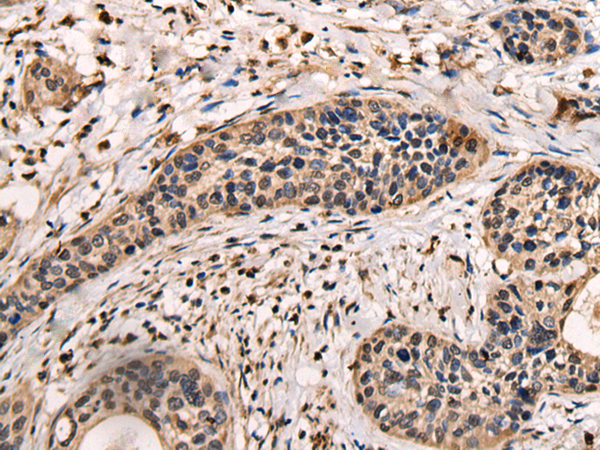

ELISA, IHC |

IHC positive control: |

Human cervical cancer |